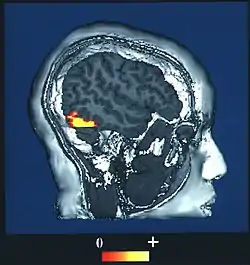

![]() Computer-enhanced fMRI scan of a person who has been asked to look at faces. The image shows increased blood flow in cerebral cortex that recognizes faces (FFA). | |